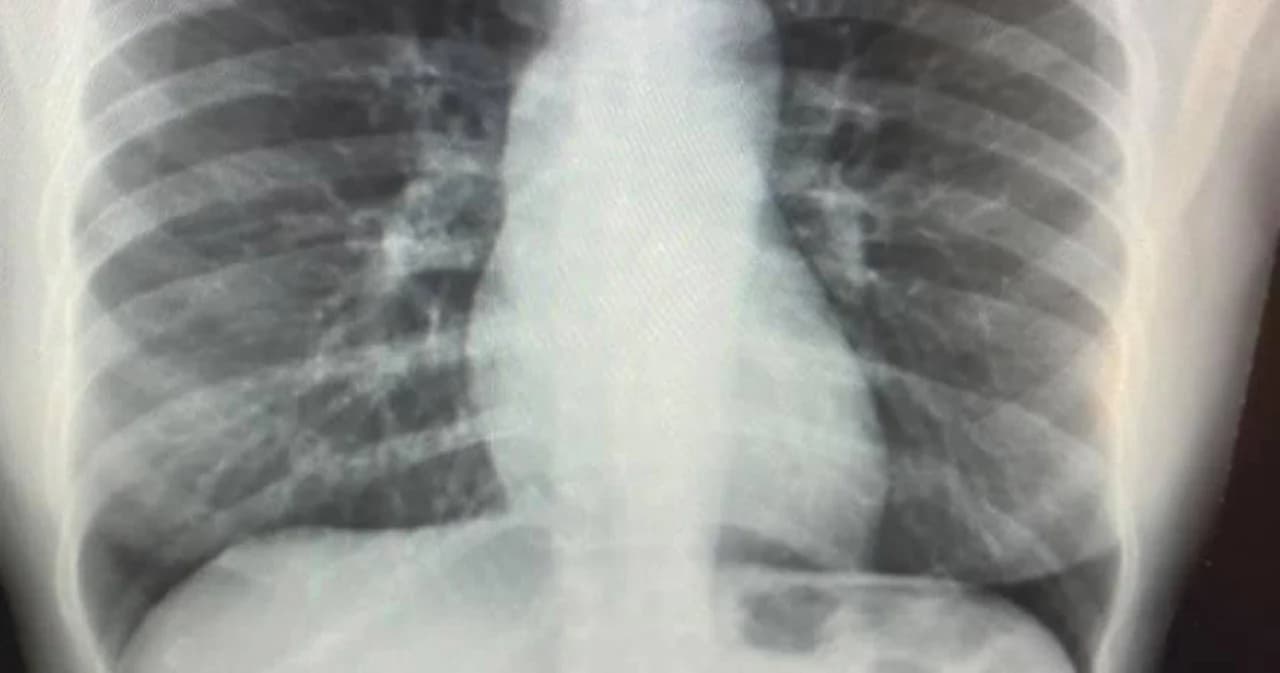

หลังฉีดวัคซีนซิโนแวคครบที่ 2 สัปดาห์ ตัวเองก็ได้ตรวจระดับ NAb ซึ่งก็สูงถึง 92.9% แต่พอติดตามไปหลังฉีดวัคซีนครบที่ 2 เดือน ค่า NAb ลดลงมาเหลือ 65.7% และในช่วงที่ค่า NAb 65.7% ก็เป็นช่วงที่ตรวจ COVID-19 detected ที่ Ct 18

real world data (ประสบการณ์ตรง) ที่เมื่อฉีดซิโนแวคไปเพียง 2 เดือนก็มีภูมิคุ้มกันที่ลดลง (ซึ่งไม่ถึงกับหายไปเลย ก็แค่ลดลง 30%) แต่ก็ต่ำพอที่จะไม่สามารถป้องกันการติดเชื้อสายพันธุ์กลายพันธุ์ได้ (คิดว่าเราน่าจะโดนสายพันธุ์ Delta แน่ๆเลย)

ซิโนแวคกันอาการรุนแรงได้ไหม (เพราะดูจากค่า Ct ที่ 18 ก็แสดงว่าปริมาณเชื้อในตัวเราก็น่าจะเยอะพอควร) อันนี้จะมาเล่าให้ฟังครั้งหน้าว่าอาการเราเป็นอย่างไร